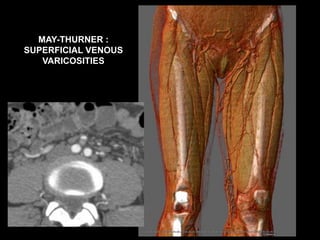

MAY-THURNER :

SUPERFICIAL VENOUS

VARICOSITIES

41 YO F, May - Thurner